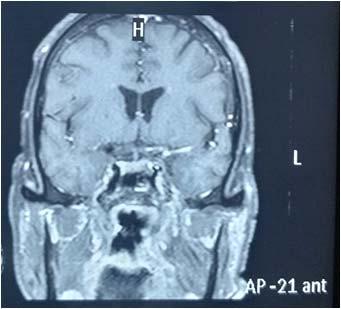

Among the metabolically abnormal patient’s population 20% (n=3) had Hypoglycemia, 40%(n=6) presented with Dyselectrolytemia, 26.67% (n=4) had Uremia, 13.33% (n=2) presented with Hepatic encephalopathy. Overall, 31 patients underwent Lumber puncture, of which CSF report shows abnormality in 11 (35.48%) cases and normal in 20 patients (64.51%). Abnormal CSF report suggesting viral meningoencephalitis found in 46% (n=5), bacterial meningitis in18% (n=2), Tuberculous Meningitis in 27% (n=3), Aseptic meningitis in 9% (n= 1). All 65 subjects underwent CT scan brain among which MRI Brain also done in 55 cases. CT findings is normal in 44.62% (n=29), abnormal in 55.38% (n=36). The most common CNS lesion on CT scan was infarction in 10.77% followed by ring lesion in 9.23% and intracerebral Hemorrhage in 7.96%. We observed cerebral infarction is causative factor of Seizure in female (15%) but intracerebral hemorrhage and ring lesion are most common findings in male, comprising 11.11% patients at each category. The CT scan in new onset Seizure of elderly patient population revealed Infarction in 28.57%, Gliosis in 19.04% and cerebral atrophy in 14.28%. The breakup of findings in MRI Scan of 55 patients shows Hyperintensities on T2, indicating Demyelination / Inflammation/edema in12.31% followed by infarction in 10.77% and ring lesion in 9.23%. In the female population, hyperintensities on T2 MRI found in 15% and Infarction in 15% whereas among the males intracerebral Hemorrhage, Ring lesion and hyperintensities on T2 found at similar occurrence rate @11% in each of these three types of lesions. EEG was done on 80% patients (n=52) of whom 22 patients has abnormal discharge in EEG but 30 patients have normal presentation. Among 65 patients one female expired due to Acute Demyelinated Encephalomyelitis (ADEM) and two males expired one due to Hemorrhage, another one with CNS infection when undergoing treatment indoor.

We found a strong positive correlation between abnormal EEG and abnormal Neuroimaging with Correlation coefficient of 0.902, (P- Value 0.0138) but almost no correlation found between normal EEG with normal Neuroimaging (Figs 1-4).

About 23% of patients with adult onset first seizure has metabolic derangement and the most common etiology was Dyselectrolytemia. The most common Central Nervous System (CNS) Infection as detected by CSF study was viral meningoencephalitis followed by Tuberculous Meningitis. The most common CNS lesion detected by CT studies as well as by MRI Brain was infarction and ring lesion, the two Neuroimaging studies corroborated in 75.38% of Seizure patients. Abnormal discharge in EEG found in34% cases. In majority patients EEG report was normal. EEG abnormality was more common in patients with Focal Seizure rather than GTCS patients. Thus, the most common etiology of first Seizure onset at adult age over 18 years were metabolic derangements (16.92%), CNS Infection or Inflammation (15.38%) and intracerebral Space occupying lesion (15.38%), usually ring lesion, tumors and Metastasis. Idiopathic Seizure found in 7.69% patients. The Correlation between abnormal Neuroimaging and abnormal EEG is strongly positive and statistically significant (P -Value = 0.013) but the same is not true in cases of normal Neuroimaging and normal EEG findings.